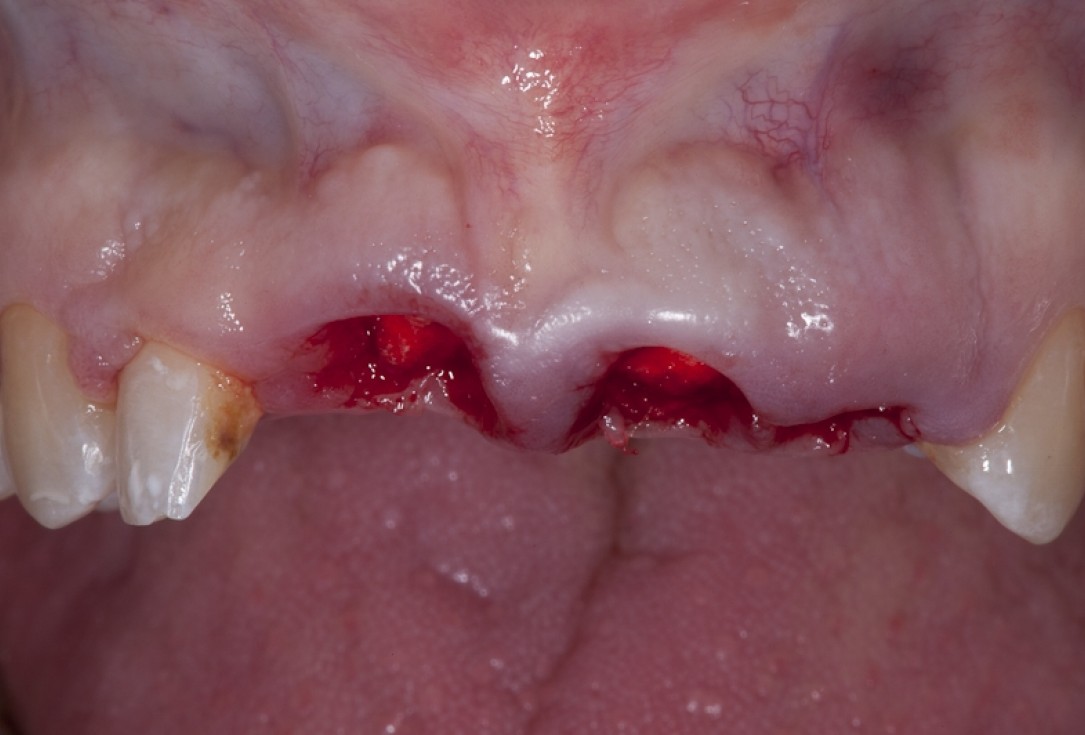

Socket preservation with permamem® - Dr. R. Rannula

Situation after tooth extraction.